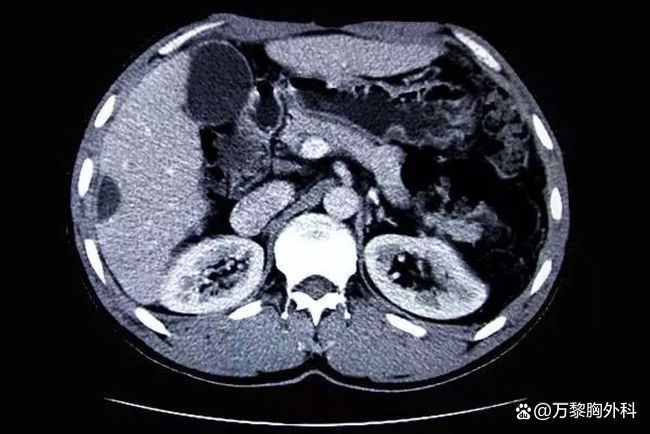

Ct是一项先进的医学方法,可以用来检查各种疾病以及观察体内是否存在病变组织,但是ct的医学方法是会影响到身体健康的,一般危害是不大的,不适合备孕的女性使用ct对身体是有辐射的,辐射的时间一般在三个月左右就可以消失的,而且ct的时间越长会导致皮肤出现灼伤的症状ct的辐射多久才能消失呢1三个。